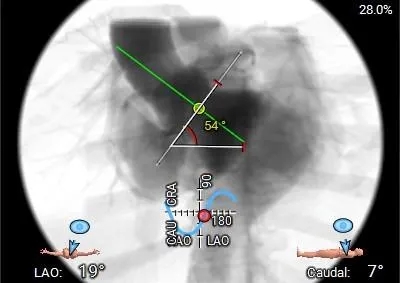

左室增大,瓣环夹角54°,非横位心。

工作体位

右窦居中

左冠切线

左右重叠